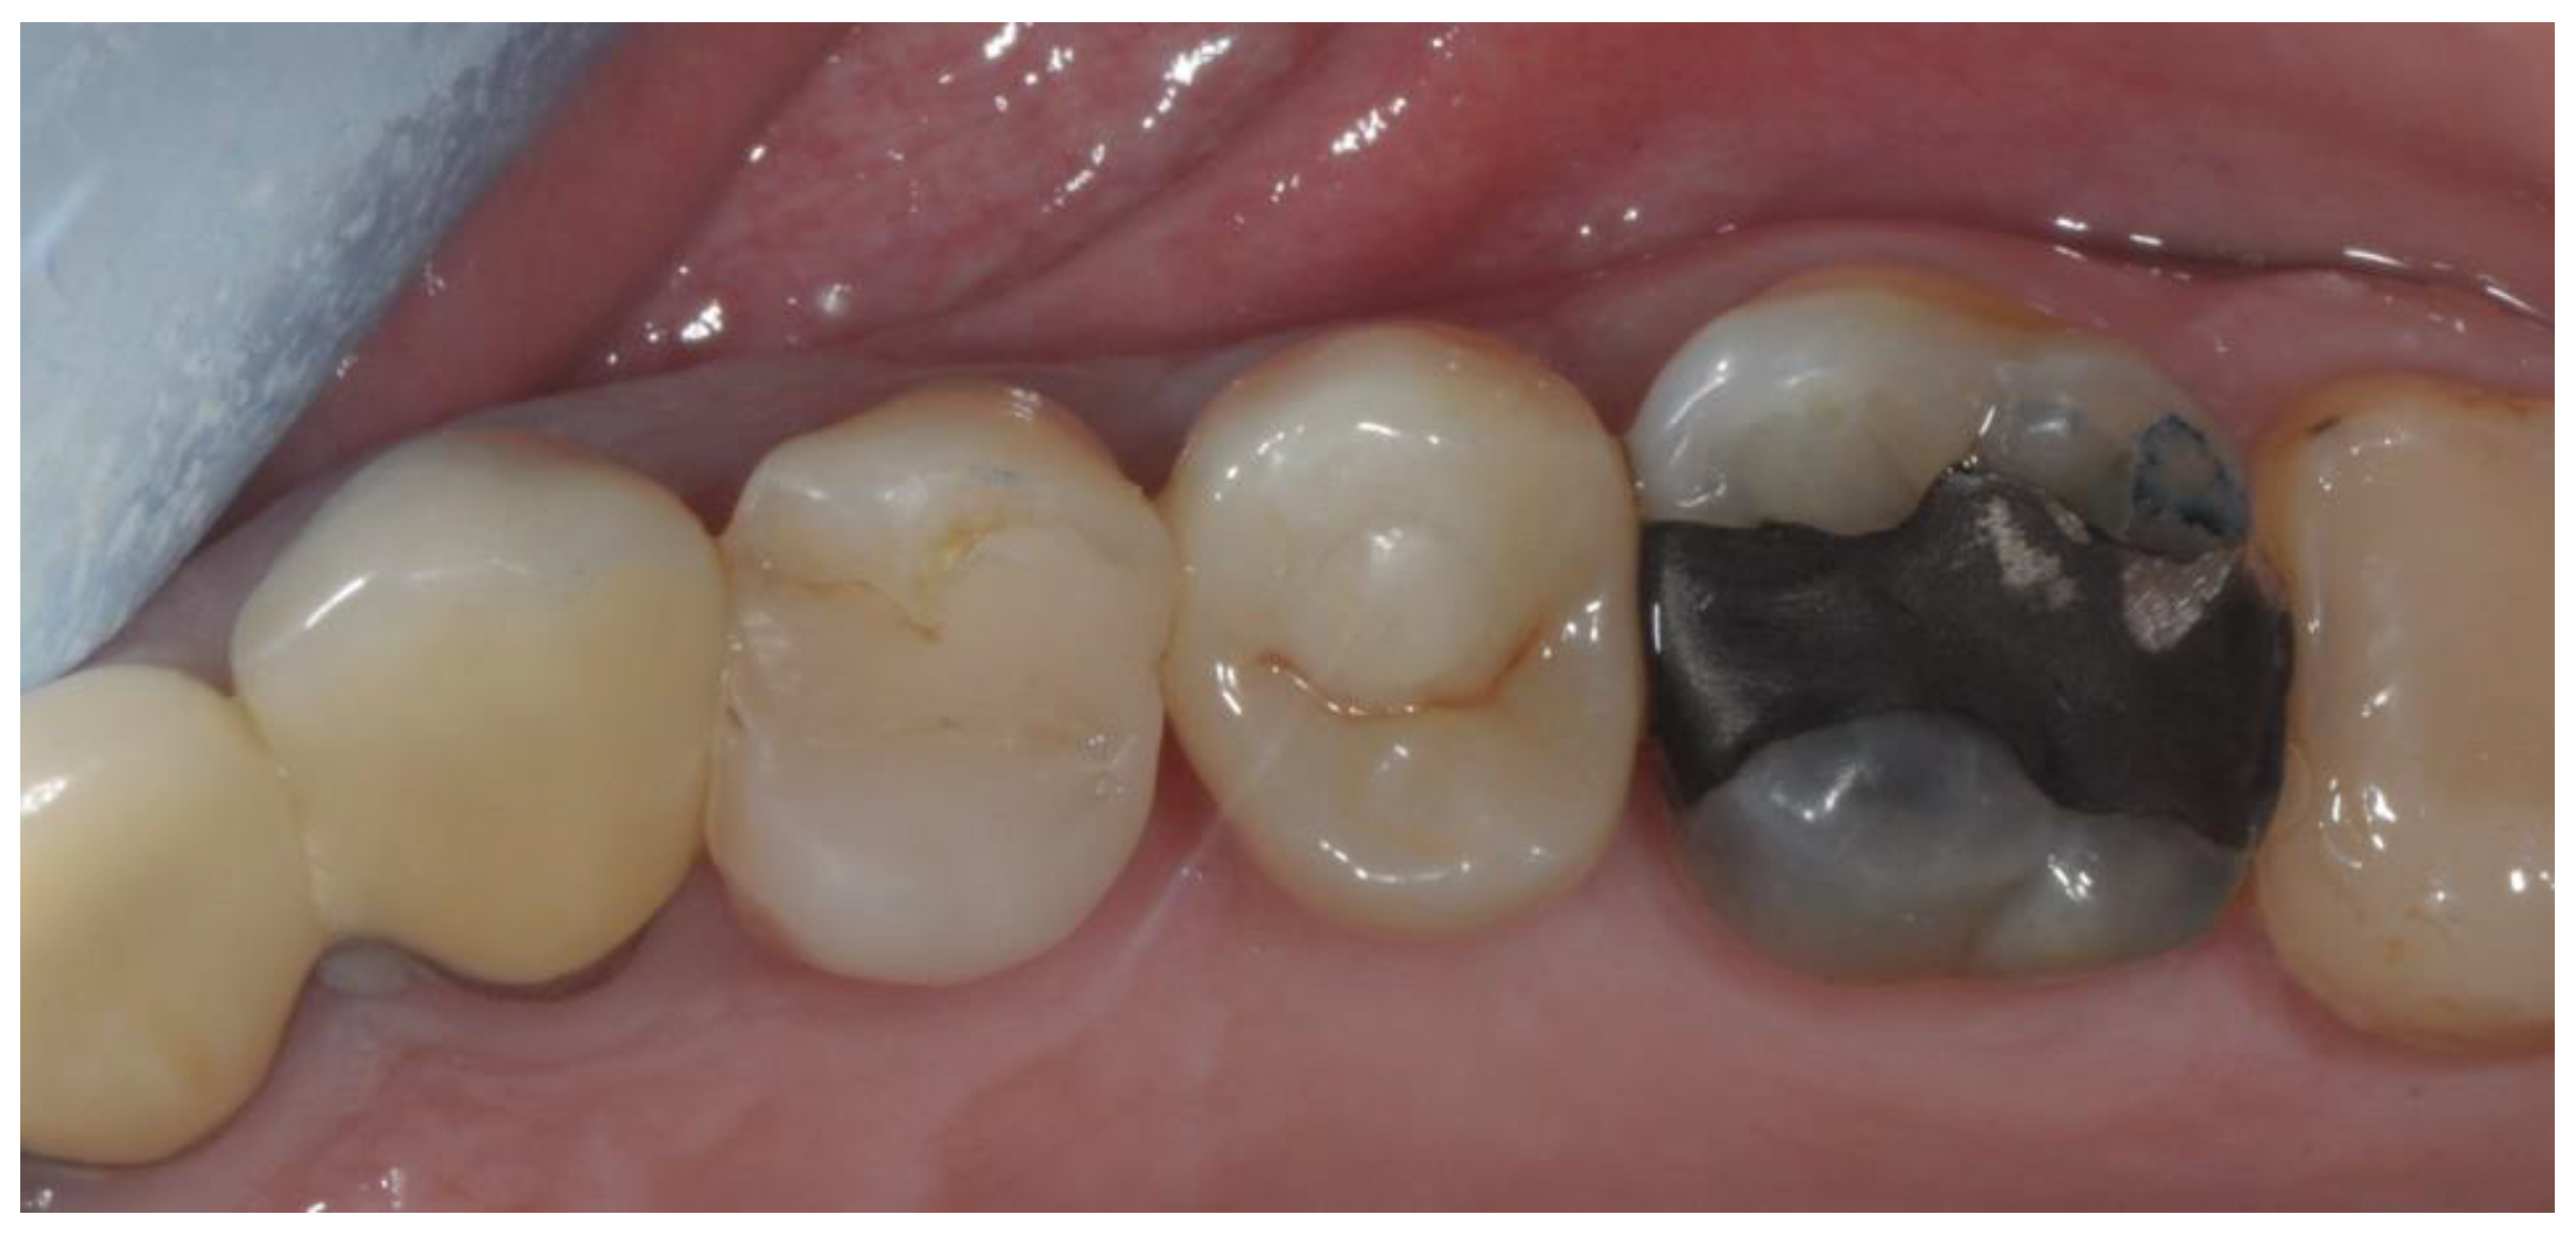

2. Materials and Methods

2.3. Prosthetic Protocol